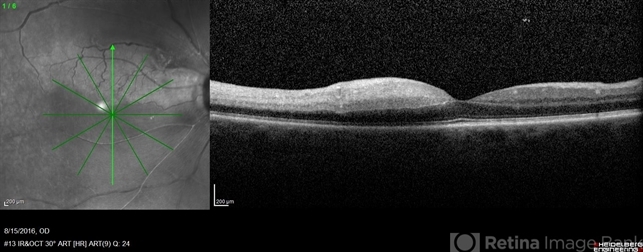

- central retinal artery occlusion (CRAO), cilioretinal artery, cilioretinal sparing

- 60-year-old female with sudden loss of vision of right eye.